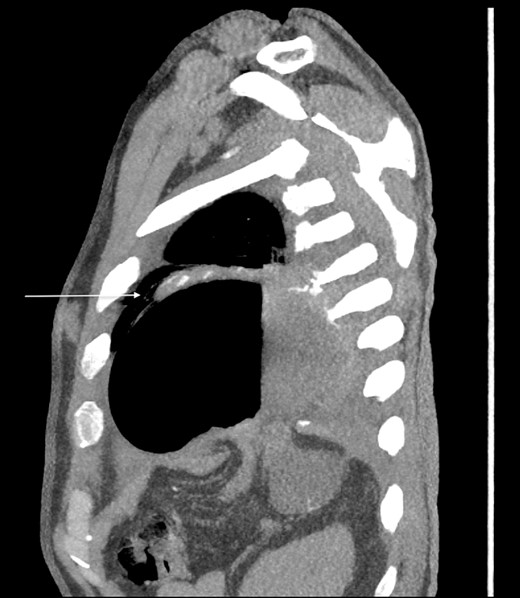

Thirty-seven days after the initial visit, the patient returned to the emergency department with burning epigastric pain that radiated to the left upper chest and hematemesis. Vital signs revealed tachycardia and hypertension. A comprehensive physical exam was significant for decreased breath sounds at the left base and tenderness in the left upper quadrant without signs of peritonitis. Pertinent laboratory findings showed leukocytosis with a left shift and thrombocytosis. A chest X-ray showed a significant portion of the gastric body in the left hemithorax (Fig. 1). A pulmonary CT angiogram found segmental and subsegmental pulmonary emboli in both lungs with no evidence of right heart strain and a left pleural effusion. A left diaphragmatic hernia with the “dangling diaphragm” sign can be seen on the sagittal view (Fig. 2). The coronal view shows discontinuity of the diaphragm and the “collar” sign (Fig. 3); the axial view shows the “dependent viscera” sign and thoracic fluid abutting abdominal viscera (Fig. 4).

Axial CT showing previously fractured ribs, the “dependent viscera” sign, and thoracic fluid abutting abdominal viscera.